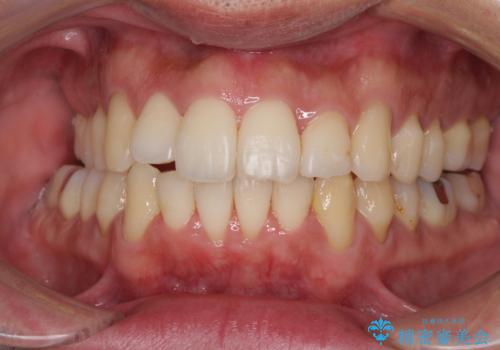

インビザラインは1日22時間を目標にマウスピースを装着することで歯列を改善するものです。

そのため、上下の歯が接触することはほとんどなく、マウスピースを介した咬合において歯列矯正が進んでいきます。

この方は元々骨格的な偏位が大きかったためか、治療中に下顎骨が上顎骨よりも右外側に誘導されて、右側の奥歯が全く咬合しない状態が続いてしまいました。

最終的にはゴムかけなどを活用して改善することができましたが、4年近い治療期間を要することとなりました。